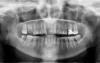

IvanK Опубликовано 9 апреля, 2013 Поделиться Опубликовано 9 апреля, 2013 Проф. гигиена + обучение гигиенеКонсультация + наблюдение у пародонтолога Удаление 16, ; (31,32,41,42)?Повторное лечение 26, далее коронкаЛечение 47?, далее коронка на него?Фанатичное отношение к гигиене: щетка, нитка, ирригатор. Запретить Себе пользоваться зубочисткойИмплантация 16, 11, 47? , 32?,42?Напоследок и самое важное: Консультация ортопеда с составлением плана лечения Ссылка на комментарий

Shushek Опубликовано 9 апреля, 2013 Автор Поделиться Опубликовано 9 апреля, 2013 Была я у ортопедов, они от моих "зубьев" в шоке, кто-то говорил удалить 21, иначе ниче не сделать, он стоит очень криво, другие ну очень с напрягом говорят, ну постараемся. Я конечно все понимаю, сама виновата. Носила когда то пластины, но ничем они мне помоч не смогли, на то время мне ничего другого наши ортодонты не могли предложить. А вот аукнулось мне все это после того, как я побежала протезироваться, но что теперь "пилить опилки", от этого легче не станет. 16 мне удалили, сейчас ортодонт, говорила еще удалить 26, ртопед говорит можно коронку и 37, насчет 21, 22 , 12, говорят сложно, у 23 оголяется корень. Вчера ходила на проф чистку, стомотолог нашел кучу маленьких дырочек . Вообще сама я склонясь больше к ортодонтии, там резец 13 стоит ближе к центру, а 12 стоит ребром, но вот я дума выдержат ли мои зубы такую нагрузку, хотя мне ортодонт сказала, что и без брекетов они тоже могут начать шататься из-за пародонтита, типа в этом случае я ничего не теряю, разве что деньги Ссылка на комментарий